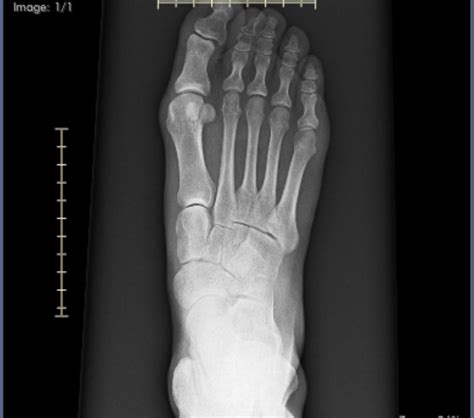

Bunions—those painful bony bumps that form at the base of the big toe—can be more than just a cosmetic concern. For many, they cause chronic discomfort, limit shoe options, and interfere with daily activities. While surgery has long been the go-to solution, growing interest in natural, drug-free approaches has led people to seek effective alternatives. If you’ve been searching for “finally a way to shrink bunions fast without surgery,” welcome—this article reveals science-backed, natural strategies that may help reduce bunion size safely and sustainably.

Bunions, medically known as hallux valgus, develop when the big toe shifts outward and the joint swells, forming a prominent bump. Several factors contribute to their formation, including genetics, tight shoes, foot trauma, and structural imbalances. Although some Bunions gradually worsen, spontaneous shrinkage isn’t common. That’s why effective correction requires targeted, gentle interventions.